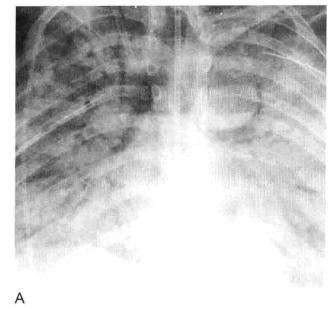

图1 实变:均匀致密影、纹理遮盖,空气支气管征和CT血管造影征

A. 肺水肿所致的右肺实变。可见双侧实变肺内 空气支气管征,肺血管模糊;B.右肺中下叶肺炎患者增强CT显示病变区均匀实变、肺体积保持不变,空气支气管征(黑色箭头)和致密学观影(白色箭头),其密度高于邻近实变肺组织(即“CT血管造影”征)